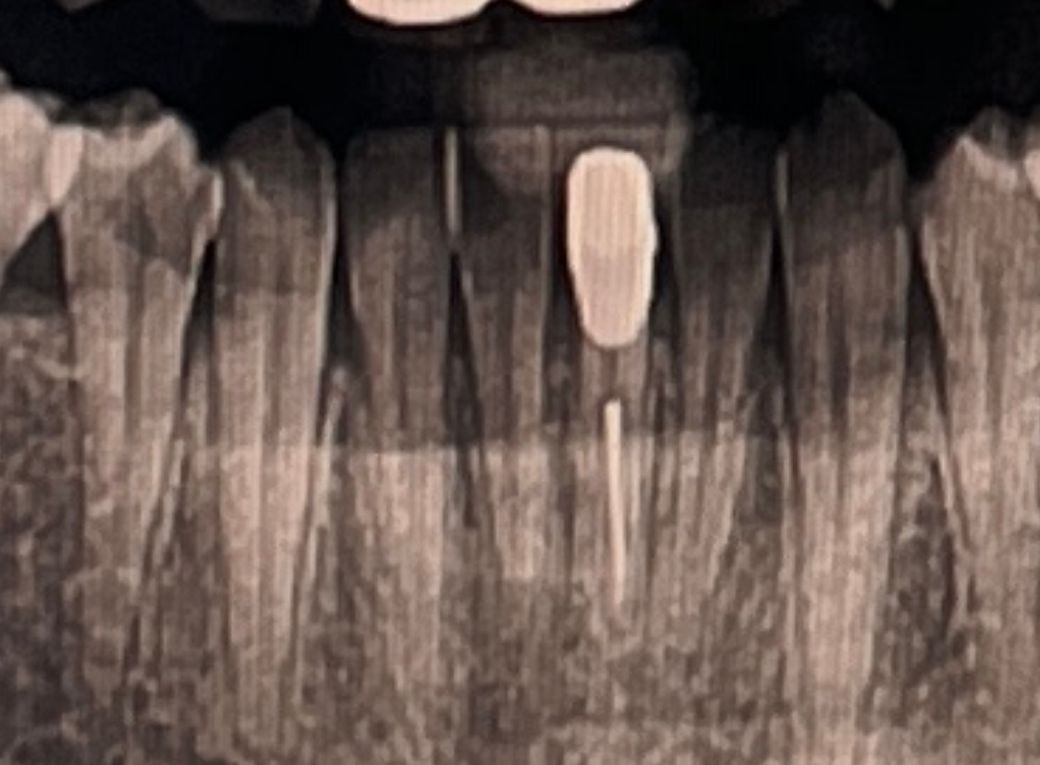

혹시 크라운 씌운 아랫니인데 무슨 문제가 있나요?

신경치료 하고 씌운지 오래 된 아랫니입니다. 화질이 좋지는 않지만 혹시 무슨 문제되는 사항이 있는지 여쭤보고싶어서 질문드립니다.

엑스레이에서는 염증이나 기타 특정한 소견이 보이지는 않는 것 같습니다. 화질때문에 정확히는 모르겠습니다.

엑스레이 상으로 크게 문제가 잇어 보이진 않습니다. 관리를 잘하시면서 사용하시면 될것같습니다.

이정도 화질의 사진 가지고는 평가할 수 있는게 제한적입니다. 특별히 신경치료가 아주 잘못되었거나 그래보이진 않습니다.

사진으로는 정확한 확인이 어려워 보입니다.

크게 문제는 없어보이지만 불편감이 있다면 치과에서 진료를 받아 보는것이 좋습니다.